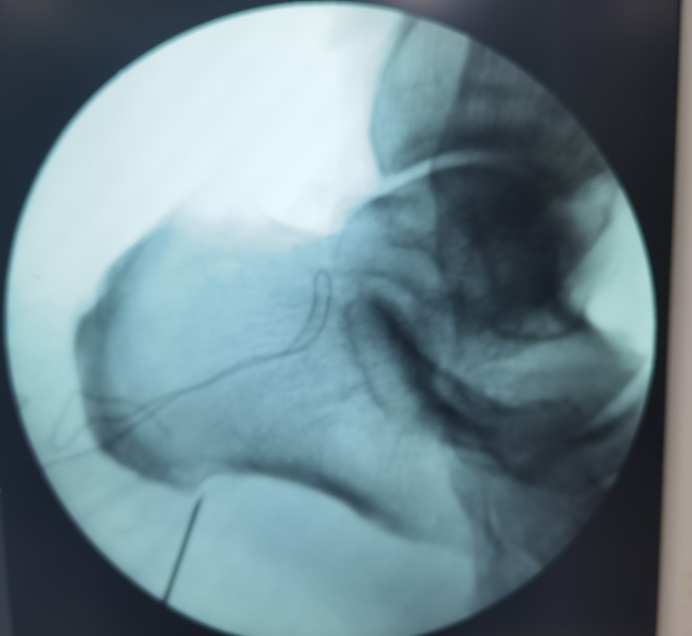

对于这类顽固性足跟痛患者,神经射频消融术提供了一个微创选择。它不是传统意义上的“大手术”,也不是把脚底切开,而是在精准定位下,用很细的射频针作用于疼痛相关神经靶点,减轻疼痛信号传导,从而达到镇痛效果。

它的特点主要是:创伤小、针眼小、局麻下可完成、恢复相对快。对那些疼痛时间长、保守治疗效果不好、又不想接受更大创伤治疗的患者来说,是一种可以考虑的办法。

69岁的朱先生,左足跟疼痛已有一年,近1个半月症状加重,尝试过多种保守治疗,疼痛始终没有明显缓解。后来接受了我院关节外科的神经射频消融术治疗,整个过程不到半小时,术后疼痛得到了很大缓解,生活状态也明显改善了。